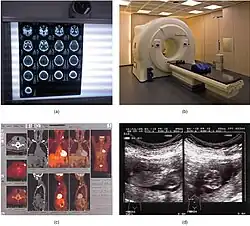

Entre as tecnologias mais comumente utilizadas tem-se: radiografia, mamografia, ultrassonografia, tomografia computadorizada, ressonância magnética, radiologia Intervencionista, angiografia, densitometria Óssea e tomografia por emissão de positrons.

Na medicina moderna, imagiologia médica tem sofrido grandes avanços. Hoje, essa capacidade de obter informações sobre o corpo humano tem muitas aplicações clínicas úteis. Ao longo dos anos, diferentes tipos de imagens médicas foram desenvolvidos, com suas próprias vantagens e desvantagens. Há métodos baseados em raios-X convencionais, tomografia computadorizada (TC) e mamografia. Para melhorar a imagem de raios X, os agentes de contraste podem ser utilizados, por exemplo, para exames de angiografia. A imagiologia molecular é utilizada na medicina nuclear e utiliza uma variedade de métodos para visualizar os processos biológicos que ocorrem nas células dos organismos. Pequenas quantidades de marcadores radioactivos, chamados produtos radiofarmacêuticos, são utilizados para imagiologia molecular. Outros tipos de imagens médicas são a ressonância magnética (MRI) e imagens por ultrassom. Ao contrário dos raios-X convencionais, CT e Molecular Imaging, a ressonância magnética e o ultrassom operam sem radiação ionizante. A RM utiliza campos magnéticos fortes, que não produzem efeitos biológicos irreversíveis conhecidos nos seres humanos.[4]

Os vários métodos de imagiologia diferem de radiologia de acordo com dois eixos mais informações de imagens, a resolução espacial (detalhes anatômicos) e informação funcional descrito (que representa o tecido composição- por exemplo, normal ou anormal). Uma amostra das modalidades de imagem mais comuns é mostrado.[2]

Modalidades de Imagens

Por quase meio século após a descoberta de raios-x por Roentgen em 1895, a imagem radiológica foi baseada principalmente na radiografia simples e contrastada. Essas imagens foram criadas expondo a película a um feixe de raios X atenuado após penetrar no corpo. A produção de raios-x e imagens radiográficas é descrita no próximo capítulo. No recente meio século, radiologia de diagnóstico sofreu mudanças dramáticas e desenvolvimentos. A angiografia convencional, a medicina nuclear, a ultrassonografia e a tomografia computadorizada (CT) foram desenvolvidas entre 1950 e 1970. Ressonância magnética (RM), radiologia intervencionista e tomografia por emissão de pósitrons (PET) foram desenvolvidas posteriormente. A radiologia convencional, incluindo radiografia de contraste e CT, utiliza radiação ionizante criada a partir de equipamentos de raios-x. A medicina nuclear usa a radiação ionizante que é emitida dos produtos farmacêuticos radioativos injetados ou injetados em várias partes do corpo. A ultrassonografia e as modalidades de RM utilizam ondas sonoras e magnetismo, respectivamente, em vez de radiação ionizante.[6]